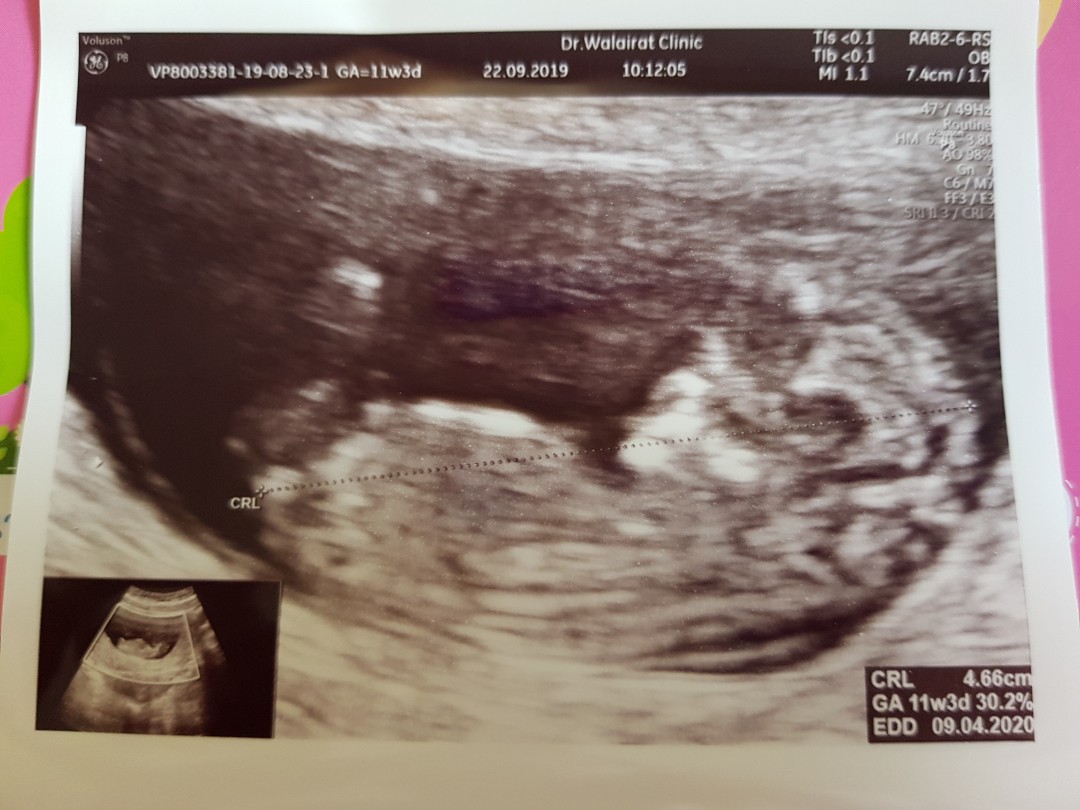

11 w 3 d คะ ตอนนี้ 13 w 6 d 😁😁